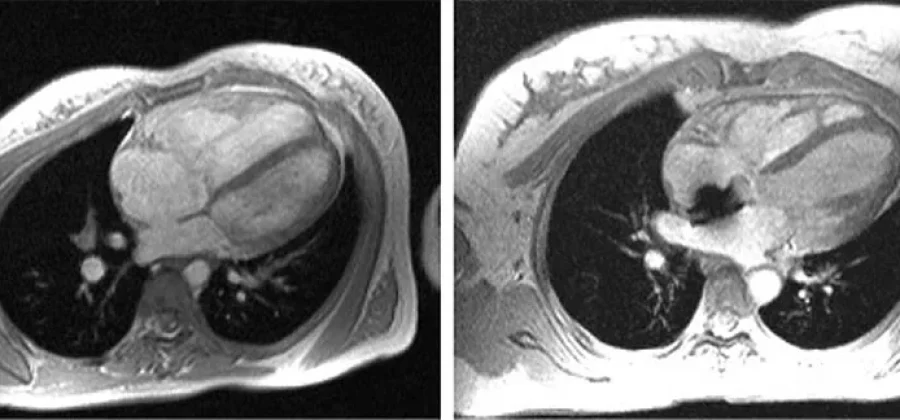

Магнитно-резонансная томография (МРТ) сердца с контрастированием — это высокотехнологичный метод диагностики, который на сегодняшний день играет важную роль в медицинской практике. Данная процедура позволяет врачам получить подробные изображения сердечной мышцы и сосудов, что необходимо для выявления различных заболеваний мамы, таких как ишемическая болезнь, миокардит и врожденные аномалии. За счет использования контрастных веществ, МРТ обеспечивает более четкое изображение, что существенно облегчает диагностику и выбор дальнейшей тактики лечения.

МРТ сердца позволяет врачу оценить не только анатомические особенности, но и функциональные параметры органа. Исследование с контрастированием помогает выявить ишемические участки миокарда, почувствовать уровень perfusion (кровоснабжения) различных областей сердца. Также оно может быть полезно в диагностике кардиомиопатий и опухолей сердца. Используемый контраст позволяет более отчетливо визуализировать сосуды и их патологии, включая стенозы и аневризмы. Такое детальное исследование значительно повышает шанс своевременного выявления возможных отклонений и, следовательно, раннего начала лечения.